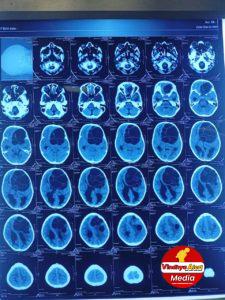

सुपर स्पेशलिटी हॉस्पिटल : रीवा में किया गया ब्रेन की गांठ का ऑपरेशन

रीवा, मप्र। सुपर स्पेशलिटी हॉस्पिटल, रीवा के न्यूरोसर्जरी विभाग में 14 साल के रीवा निवासी मरीज का हाईडेटिड सिस्ट ऑफ ब्रेन का आपरेशन डॉ. ऋषि...